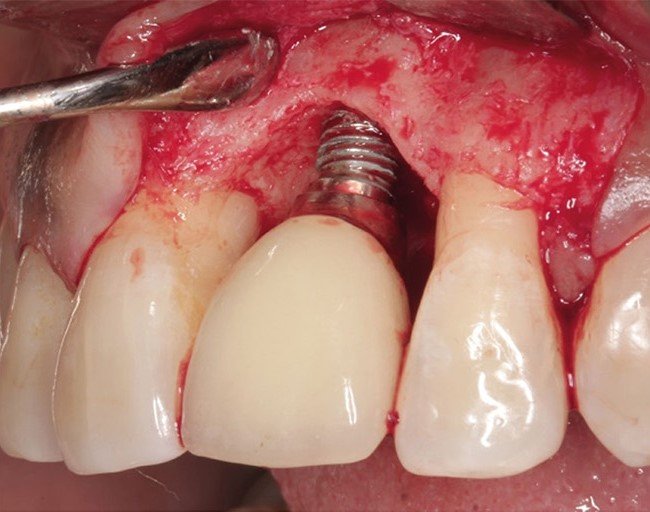

植體周圍炎(圖片來源:Zero Peri-Implantitis: A Novel Concept in Implant Dentistry)

牙周病可透過洗牙與刮治清除感染,但植體周圍炎由於植體表面有螺紋設計,不易清潔乾淨,常需搭配水雷射消毒、手術翻瓣或骨再生治療。若感染太深,甚至必須移除植體重做。

- 翻瓣清創手術

醫師會翻開牙齦,徹底清除藏在植體表面或螺紋內的細菌與感染組織,讓牙齦重新貼合。 - 骨再生治療